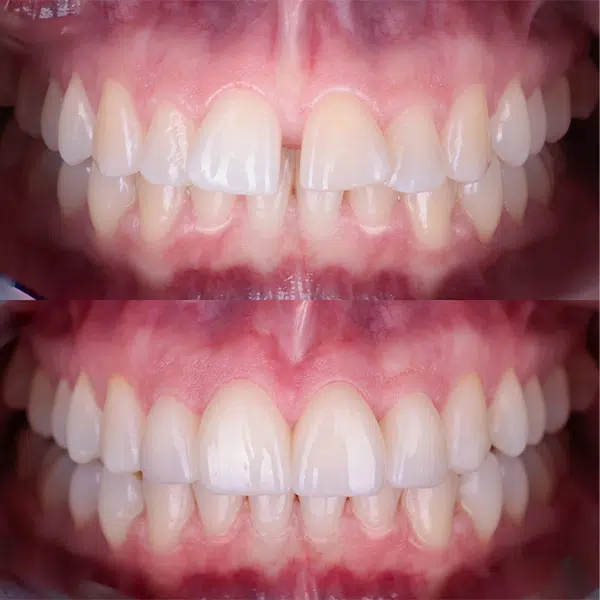

Gingiwoplastyka to procedura chirurgiczna, która polega na modelowaniu i konturowaniu dziąseł w celu poprawy estetyki uśmiechu. Zabieg ten jest bezkrwawy, bezpieczny i bezbolesny, a jego efekty są natychmiastowe i trwał

Zalety Gingiwoplastyki

- Poprawa Estetyki Uśmiechu: Korekta linii dziąseł znacząco poprawia estetykę uśmiechu, czyniąc go bardziej harmonijnym i atrakcyjnym.

- Trwałe Efekty: Efekty zabiegu są trwałe, a pacjenci mogą cieszyć się pięknym uśmiechem przez wiele lat.

Gingiwoplastyka to efektywny sposób na poprawę estetyki uśmiechu i zwiększenie pewności siebie. W naszej klinice dbamy o to, aby każdy zabieg był przeprowadzony z najwyższą precyzją i dbałością o komfort pacjenta. Dzięki nowoczesnym technologiom i doświadczeniu naszych specjalistów, możemy zapewnić pacjentom piękny i zdrowy uśmiech.